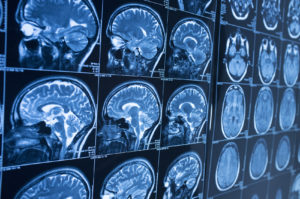

Las lesiones cerebrales

Esta es una de las lesiones más comunes asociadas con accidentes de carro.

Las conmociones cerebrales ocurren cuando el cerebro se sacude violentamente dentro del cráneo tras el impacto, o cuando la cabeza sufre un fuerte golpe durante la colisión, como golpear el volante, airbag, reposacabezas, ventana o parabrisas.

Las conmociones cerebrales de muy rara vez requieren cirugía.

Sin embargo, en algunos casos las conmociones cerebrales se producen en combinación con lesiones cerebrales traumáticas y es necesaria la cirugía. El costo de la cirugía cerebral puede ir desde $85,000 hasta $2,000,000.

Estos costos son solamente para las cirugías, no incluyendo estadía de hospital, medicamentos, etcétera.

El costo a largo plazo de la atención de las víctimas de accidentes de auto sufriendo daño cerebral varía entre $500 a $1,800,000 y más. Lesiones de espalda son muy comunes en accidentes de tráfico.